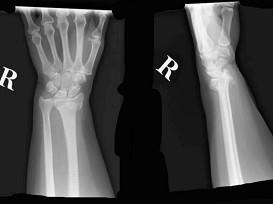

问题 六十五岁女性,摔倒时右手撑地.即感右腕疼痛,不能活动。 行X线检查如图所示为右桡骨下端骨折,该病例诊断为 ( )

选项 A、Smith骨折 B、Colles骨折 C、背侧Barton骨折 D、掌侧Barton骨折 E、Barton骨折

答案 B